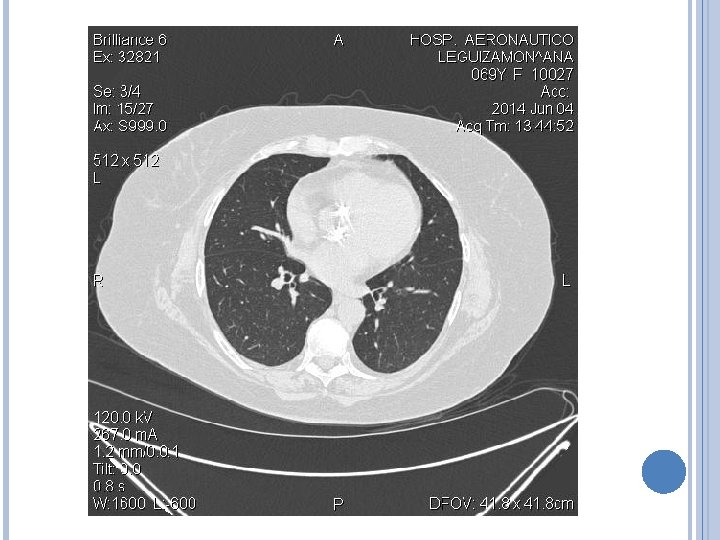

IMAGENES